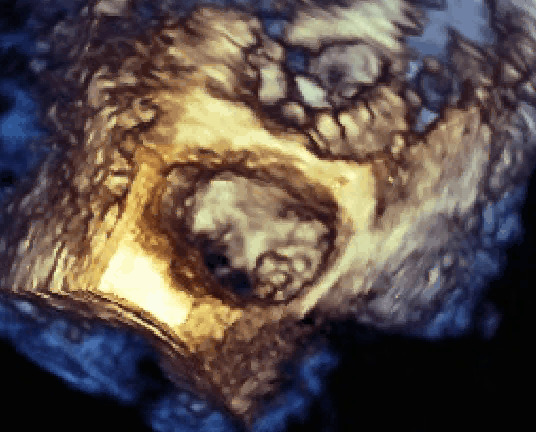

Endocardite su valvola mitrale da candida parapsilosis

Autore:

Manfredo Cerchiello